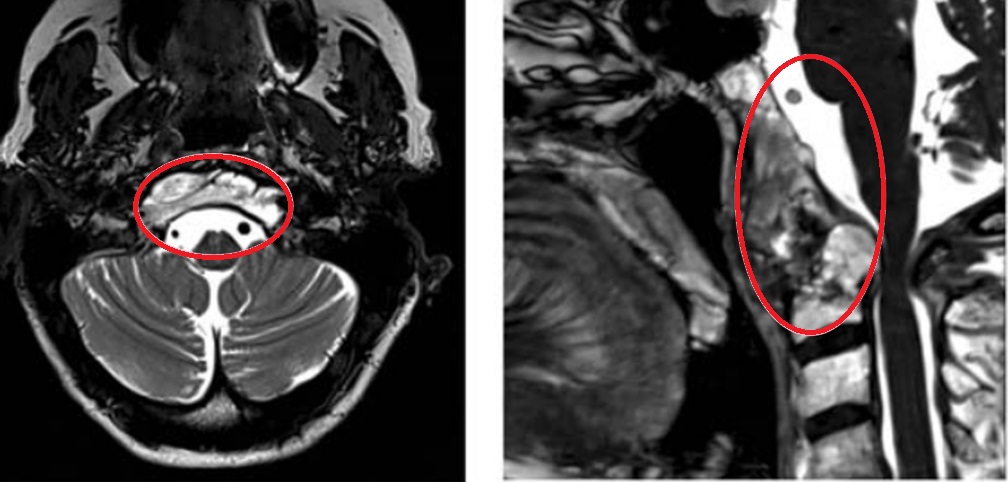

图1:内镜下鼻内镜入路前的术前影像。(A-D)MRI T2 WI显示一个较大脊索瘤延伸至椎前间隙和齿状突周围。肿瘤横向延伸至舌下管和颈静脉孔,并向内侧延伸至硬膜内间隙。肿瘤从斜坡中部延伸至枢椎齿状突周围。